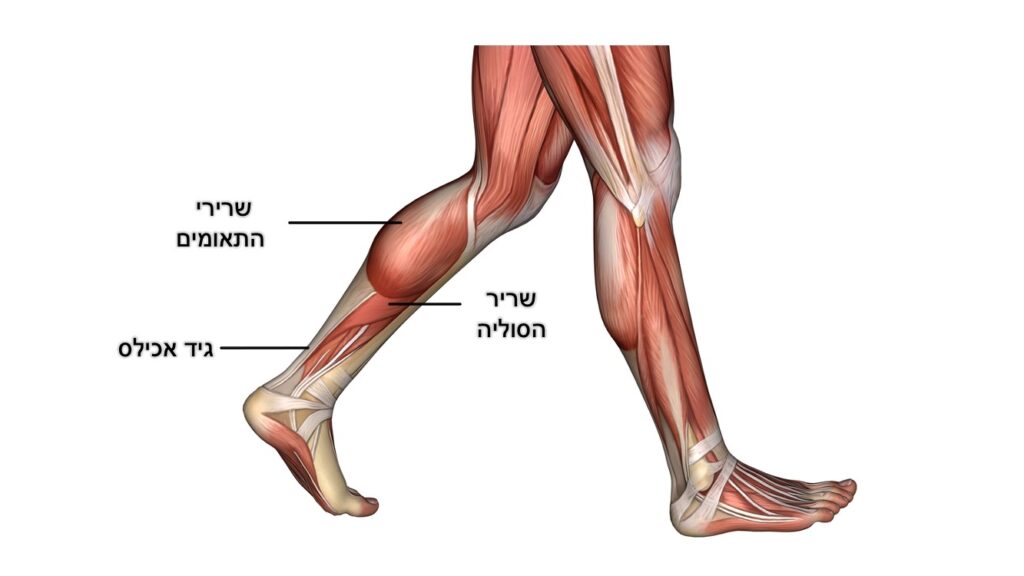

טנדינופתיה של גיד אכילס

Achilles tendinopathy

שריר התאומים ושריר הסולייה (soleus) מתחברים לעצם העקב באמצעות גיד אכילס ומייצרים תנועה של כיפוף כפי בקרסול (Plantar flexion). גיד אכילס הוא הגיד העבה בגוף האדם והוא מייצר וסופג כוחות משמעותיים בפעילות שגרה ובעיקר בפעילות גופנית.